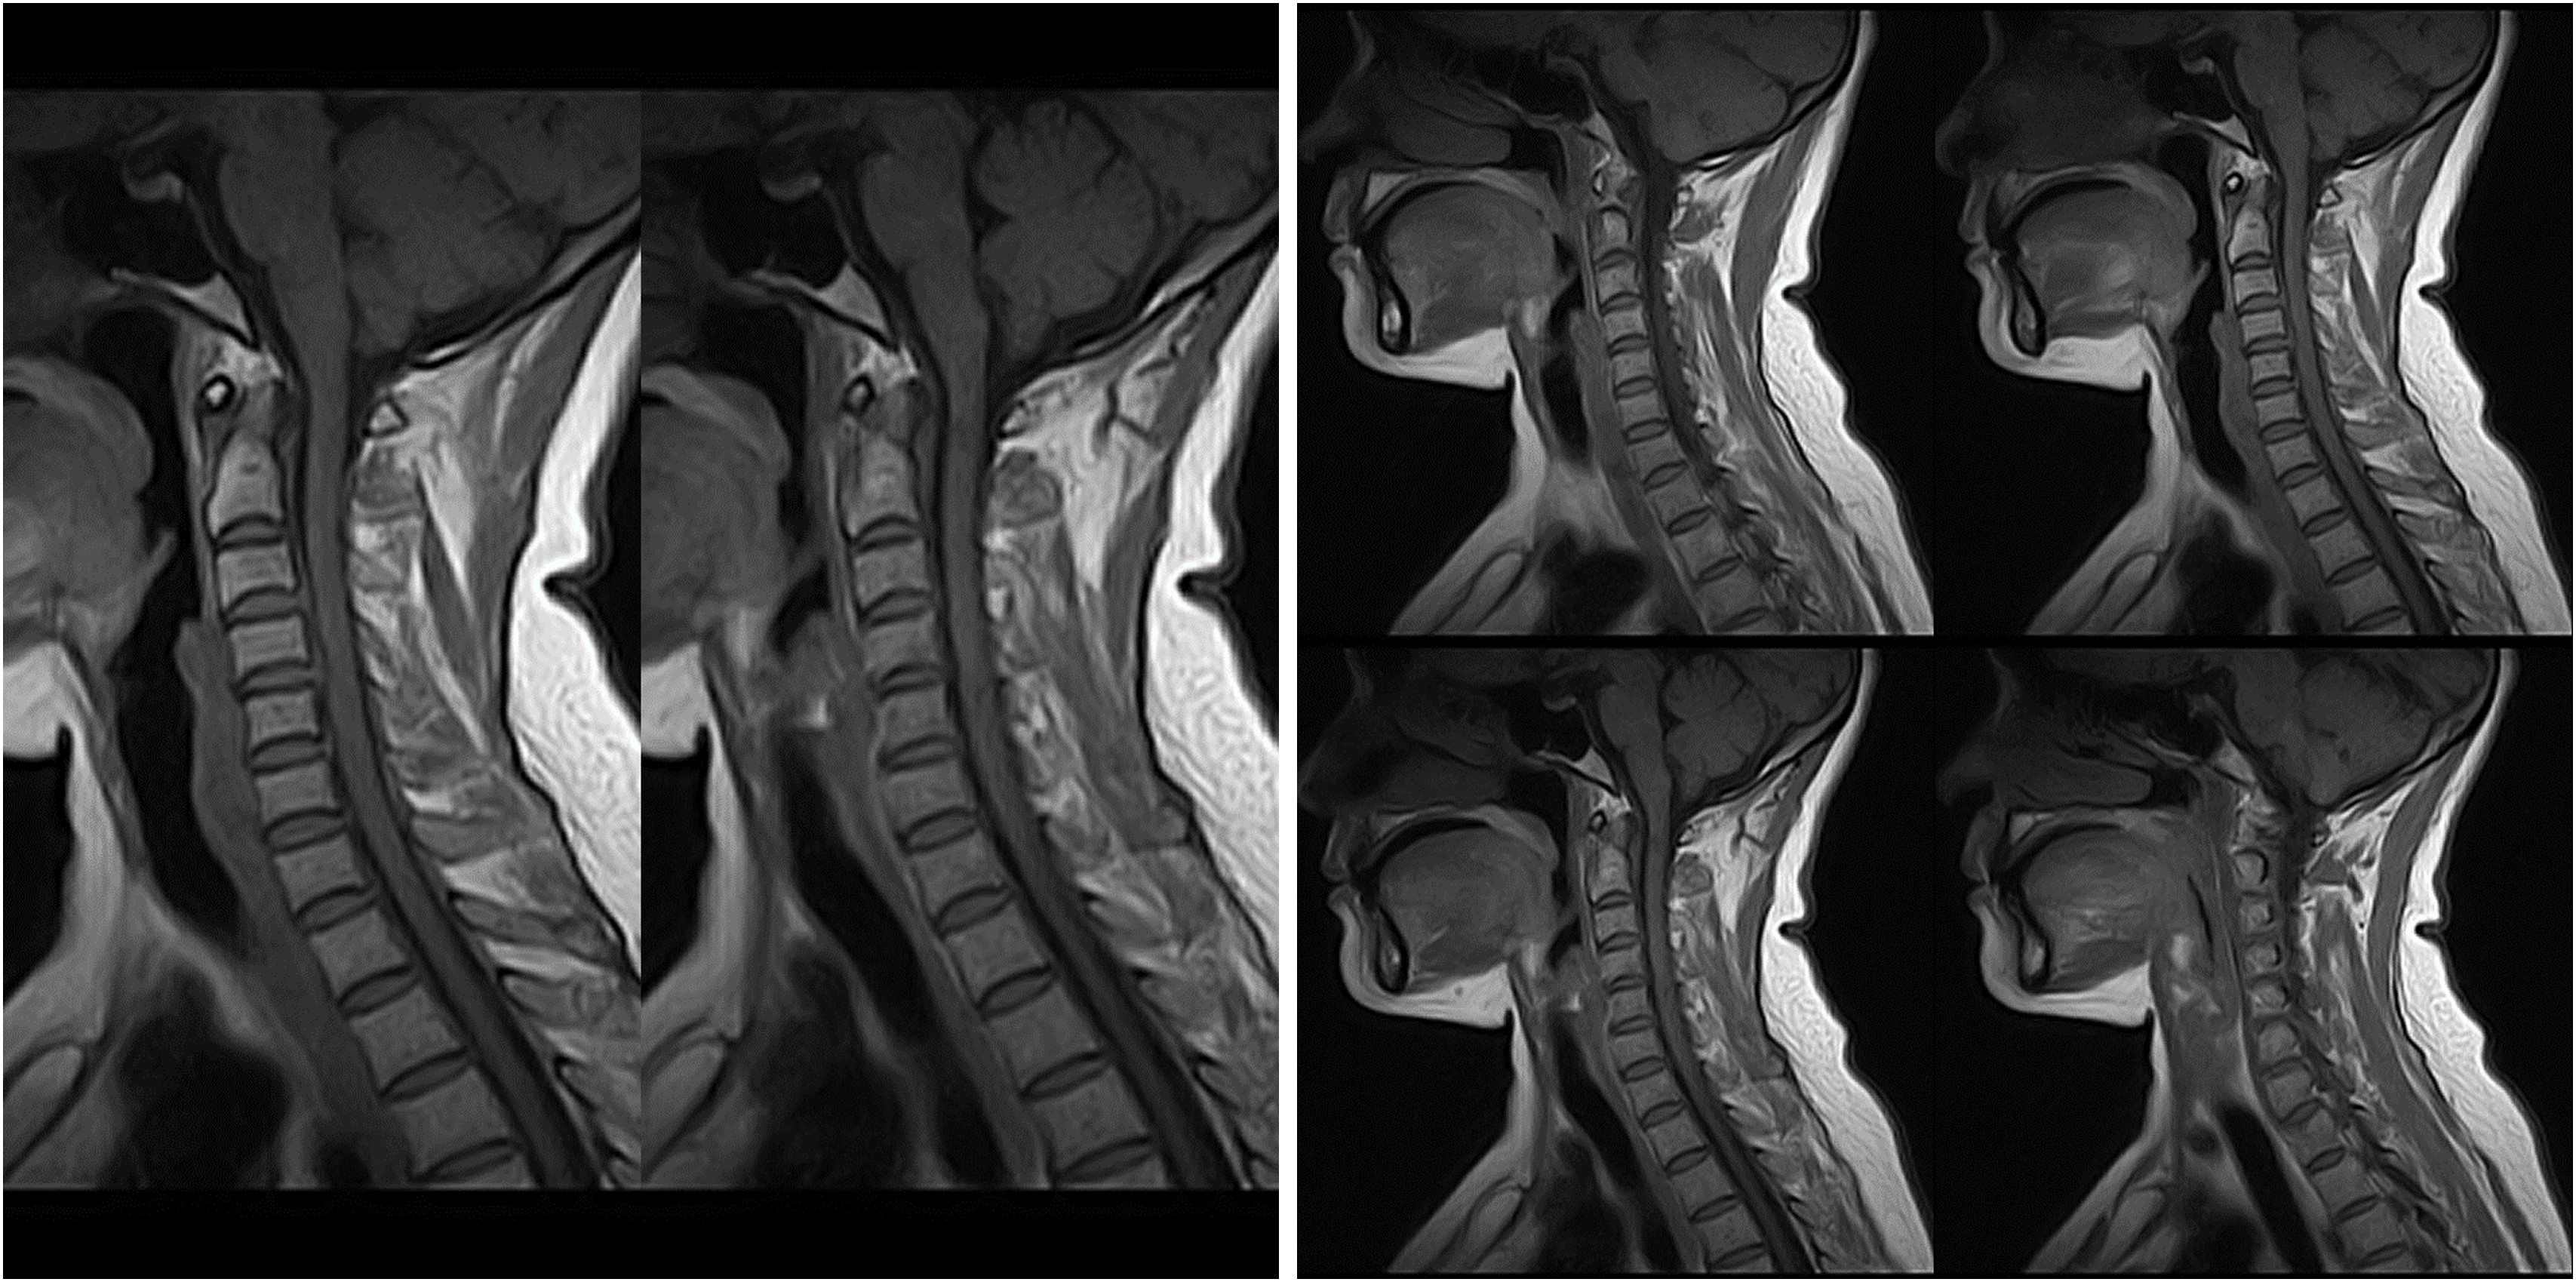

Hình ảnh lâm sàng

Giải pháp lâm sàng ấn tượng